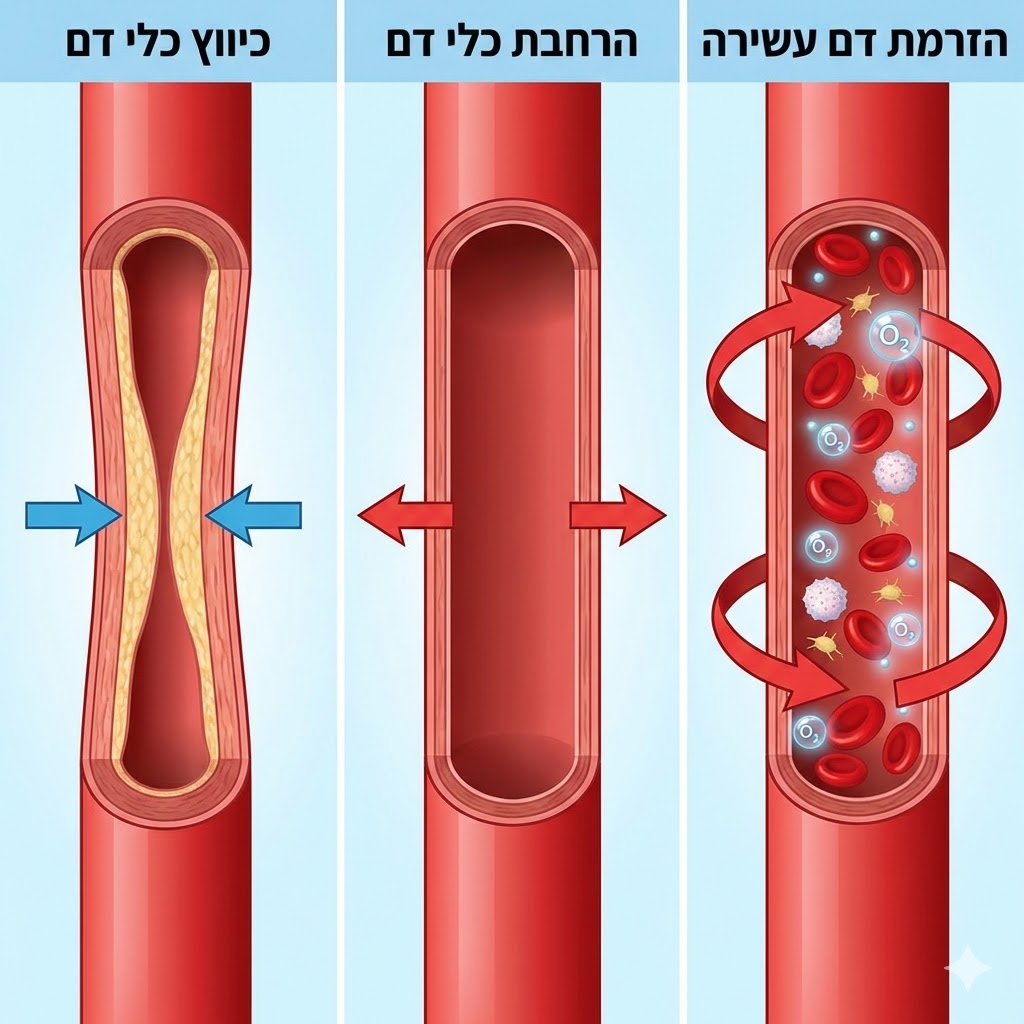

שלב 1: כיווץ כלי דם

הקור האינטנסיבי גורם לכלי הדם השטחיים להתכווץ. זה מפחית מיד נפיחות ומאט תהליכים דלקתיים באזור.

שלב 2: הרחבת כלי דם והזרמת דם עשירה

מיד לאחר מכן, כלי הדם מתרחבים בצורה משמעותית – הרבה יותר מאשר לפני הטיפול. דם עשיר בחמצן ובחומרי הזנה מוזרם לאזור המטופל, מה שמזין את הרקמות ומאיץ את תהליך הריפוי.